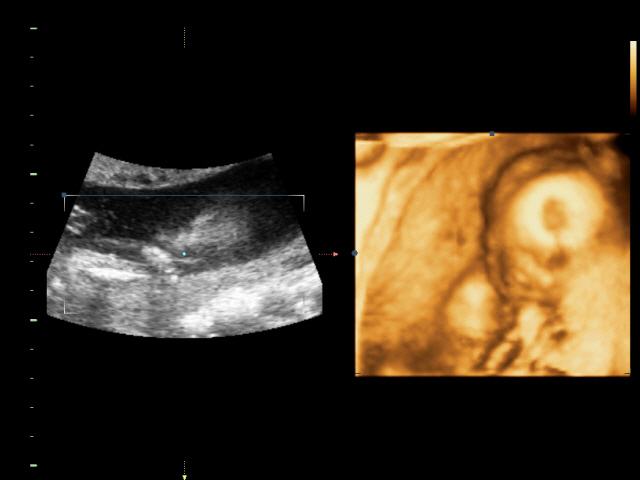

УЗИ, КТГ, доплерСходили всей семьей на 4D УЗИ! Определили нам пол окончательно и бесповоротно! Мальчик! Показали писюн! Так здорово! Я просто поверить не могу! А ведь он мне два раза снился! Настоящий реальный мужчина! Все показатели у нас в норме.